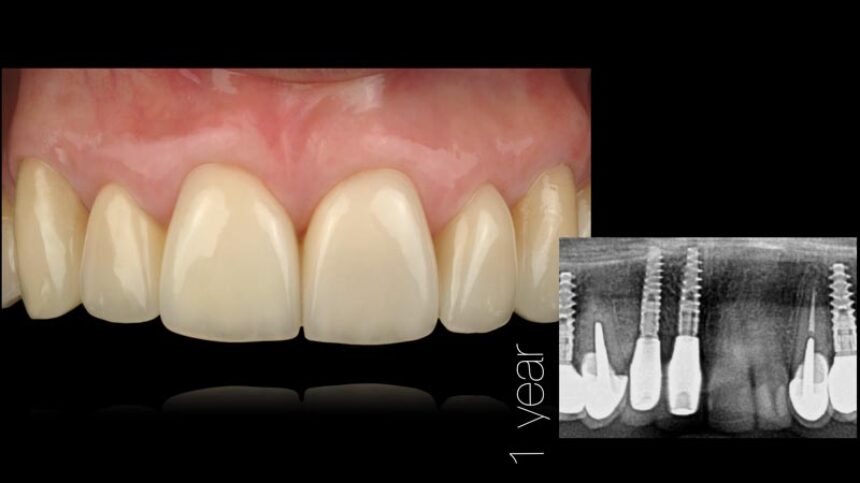

The goal to create a harmonious “esthetic” outcome around dental implants that mimics the surrounding dentition and soft-tissue condition as well as morphology is indeed difficult to create and maintain long term.

In this presentation a comprehensive approach to optimize functional and esthetic results with immediate implant placement will be discussed by blending surgical, technical, and restorative steps into one successful protocol will be presented thoroughly.

Immediate surgical and restorative protocols facilitate superior esthetic and functional success. However, strict guidelines for atraumatic intervention, implant primary stability, bone packing, connective tissue graft and preservation of existing anatomic structures must be carefully followed. Digital planning plays a fundamental role to achieve such a desired results.

On the other hand, the subepithelial connective tissue graft (CTG) is a favored option to treat and prevent gingival and peri-implant soft-tissue recessions. It is usually placed in combination with a coronally advanced flap or with an envelope flap or pouch. This lecture will focus on the difference on protocols when it comes to surgical and prosthetic criteria to treat anterior implants using as a volume maintainer only soft tissue grafting procedures. Techniques and tools will be discussed in order to reach such results around anterior implant treatments.